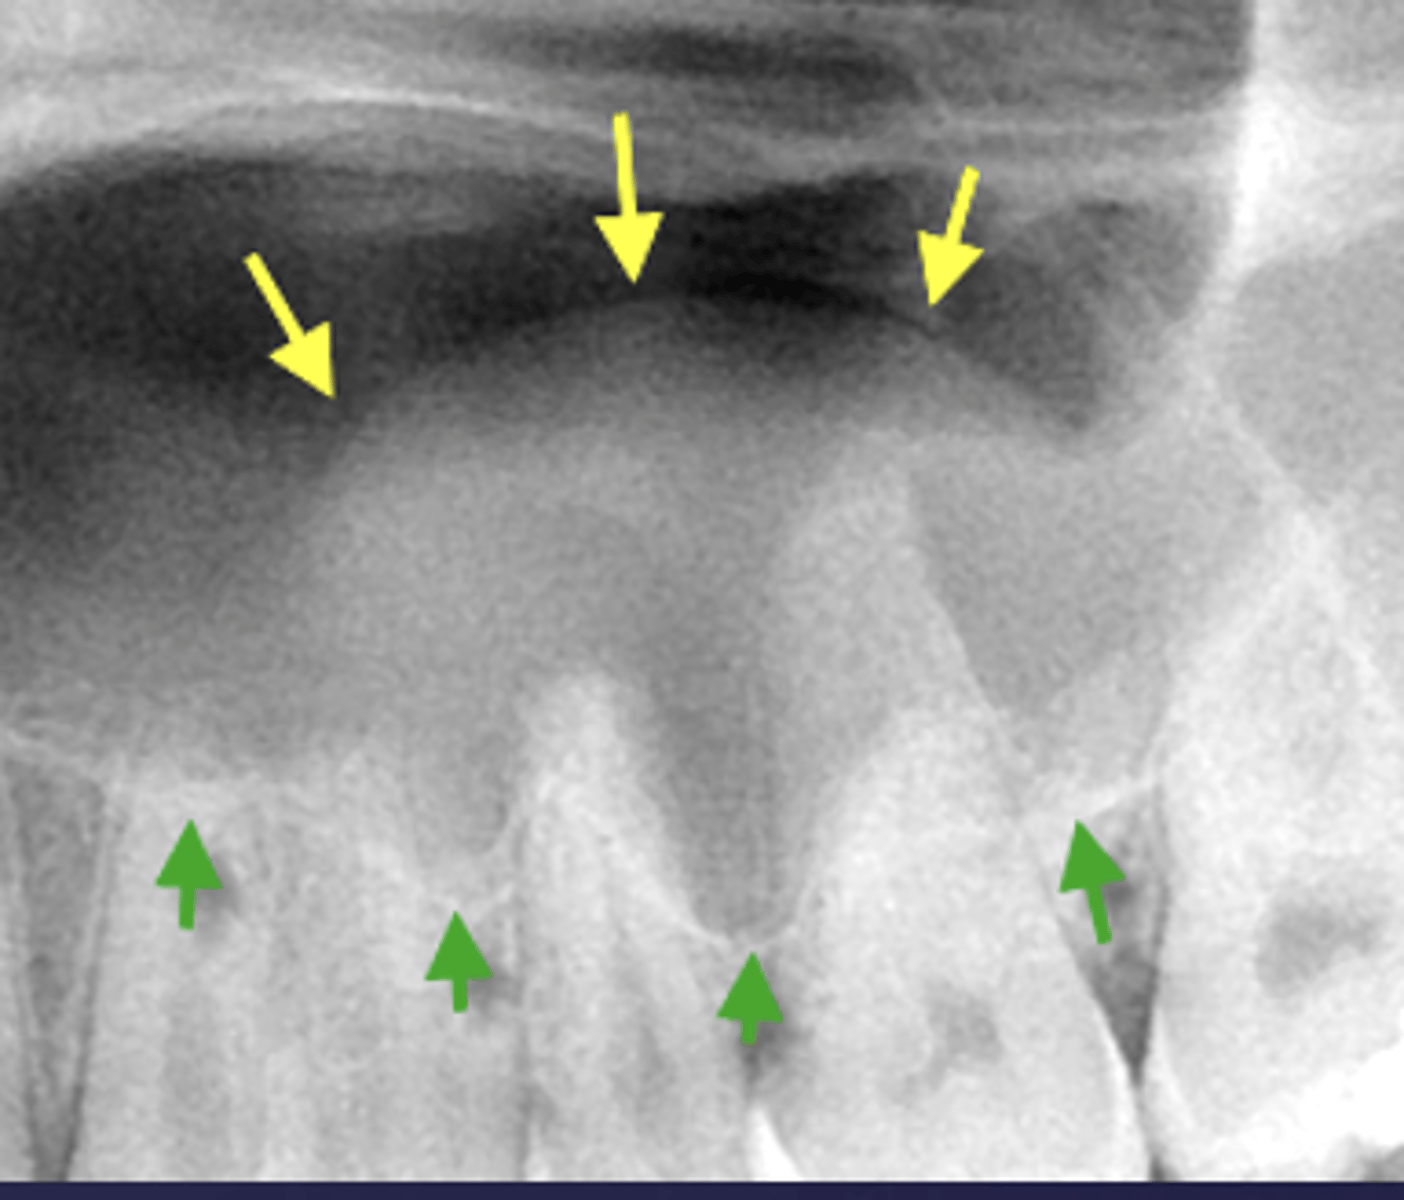

What are two defects that the arrows are pointing to?

- Widened PDL

- Sclerosis

What are the arrows pointing to?

halo sign